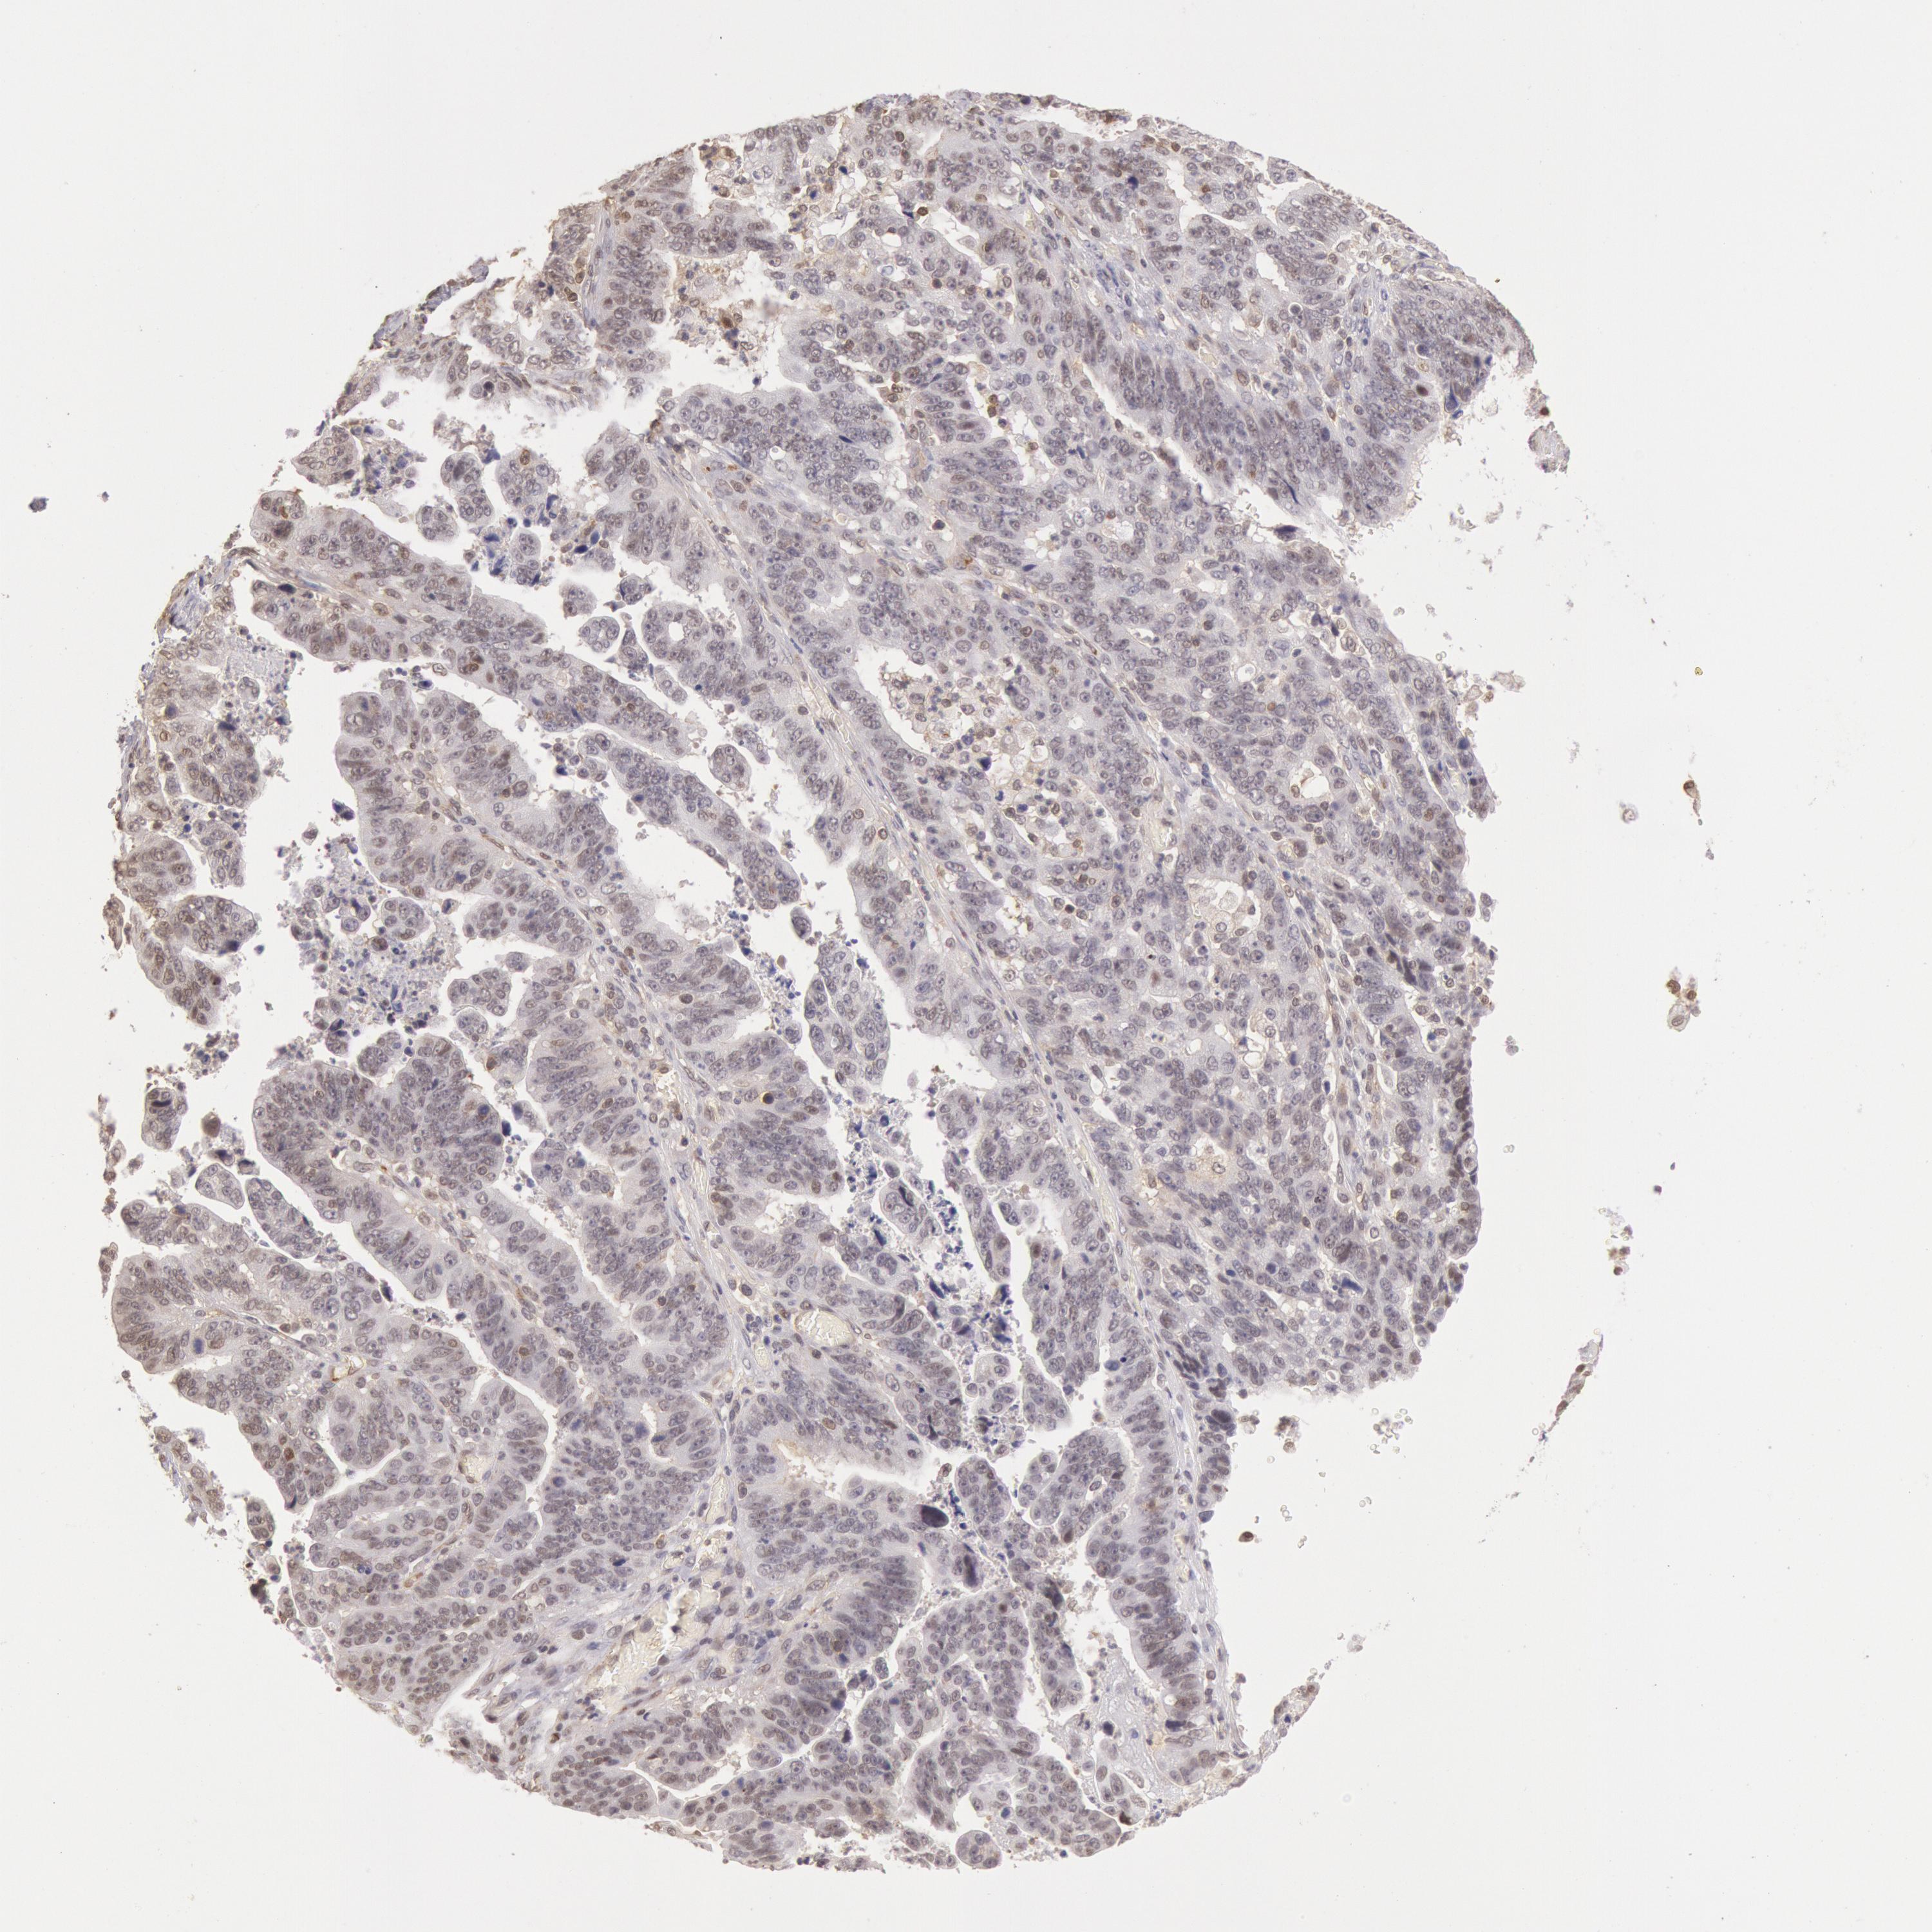

STOMACH CANCER - Protein expressioni

A mouse-over function shows sample information and annotation data. Click on an image to view it in a full screen mode. Samples can be filtered based on level of antibody staining by selecting one or several of the following categories: high, medium, low and not detected. The assay and annotation is described here.

Note that samples used for immunohistochemistry by the Human Protein Atlas do not correspond to samples in the TCGA dataset.

Antibody stainingi

Antibody staining in the annotated cell types in the current human tissue is reported as not detected, low, medium, or high, based on conventional immunohistochemistry profiling in selected tissues. This score is based on the combination of the staining intensity and fraction of stained cells.

Each image is clickable and will lead to virtual microscopy that enables deeper exploration of all samples and also displays staining intensity scores, fraction scores and subcellular localization as well as patient and tissue information for each sample.

Antibody HPA001275

Antibody CAB017442

Staining

High

Medium

Low

Not detected

Intensity

Strong

Moderate

Weak

Negative

Quantity

>75%

75%-25%

<25%

None

Location

Nuclear

Cytoplasmic/membranous

Cytoplasmic/membranous,nuclear

Adenocarcinoma, NOS

Adenocarcinoma, High grade